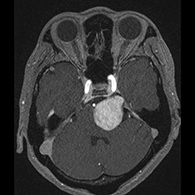

症例1) 65歳男性、頭蓋底部巨大髄膜腫、外科手術のみ

<画像所見>

巨大脳腫瘍を認める。

錐体斜台部巨大髄膜腫を認め、

神経や血管を巻き込んでいる。